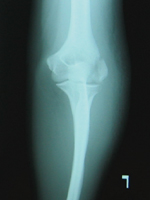

X線所見 :正面及び斜位において、左上腕骨外顆を縦方向に貫通する骨折線が認められる(図1,2)。側面では、骨折線が不明瞭。

図1 受傷時X線 正面像 |